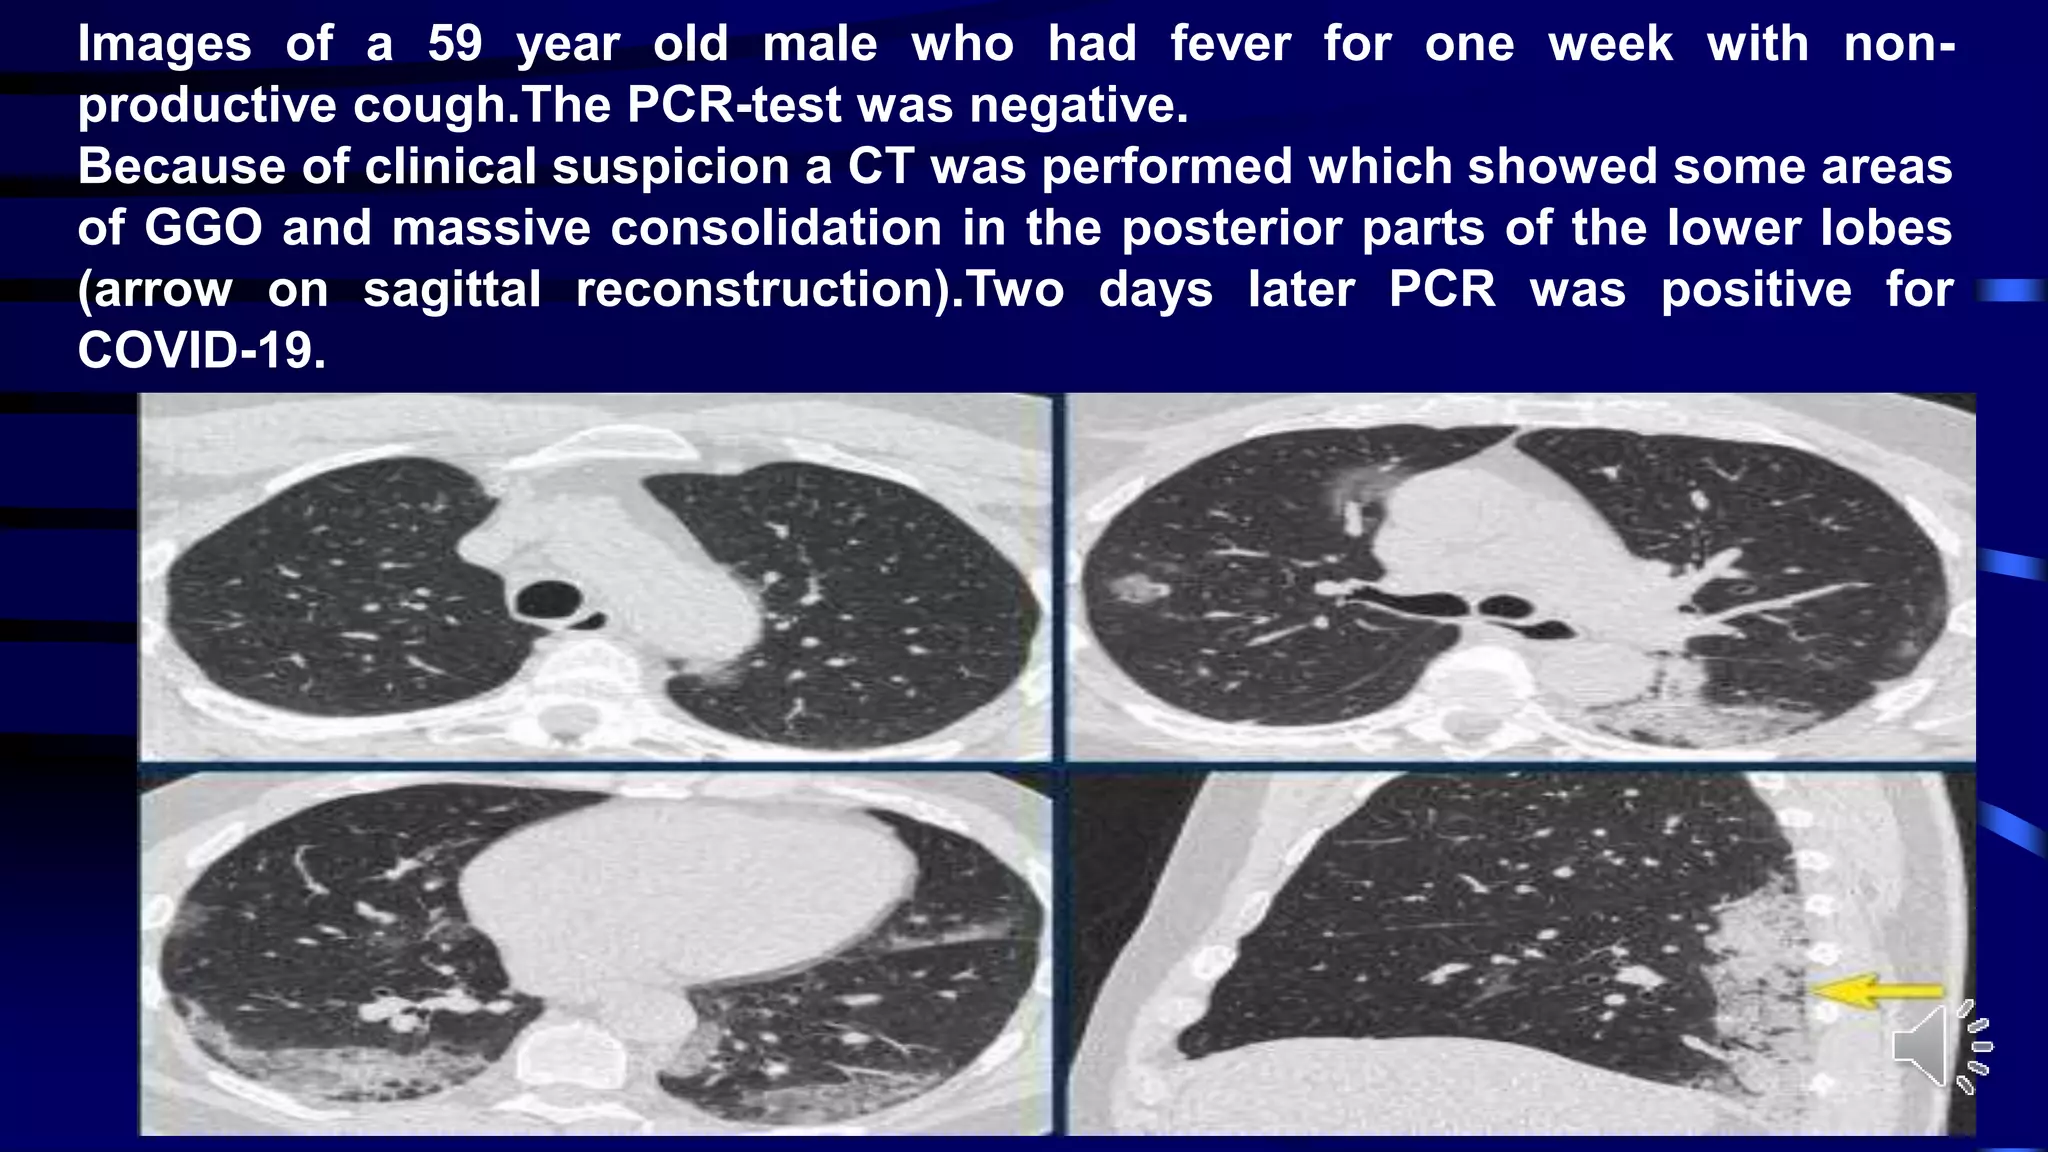

Images of a 59 year old male who had fever for one week with non-

productive cough.The PCR-test was negative.

Because of clinical suspicion a CT was performed which showed some areas

of GGO and massive consolidation in the posterior parts of the lower lobes

(arrow on sagittal reconstruction).Two days later PCR was positive for

COVID-19.

Images of a59 year old male who had fever for one week with non- productive cough.The PCR-test was negative. Because of clinical suspicion a CT was performed which showed some areas of GGO and massive consolidation in the posterior parts of the lower lobes (arrow on sagittal reconstruction).Two days later PCR was positive for COVID-19.